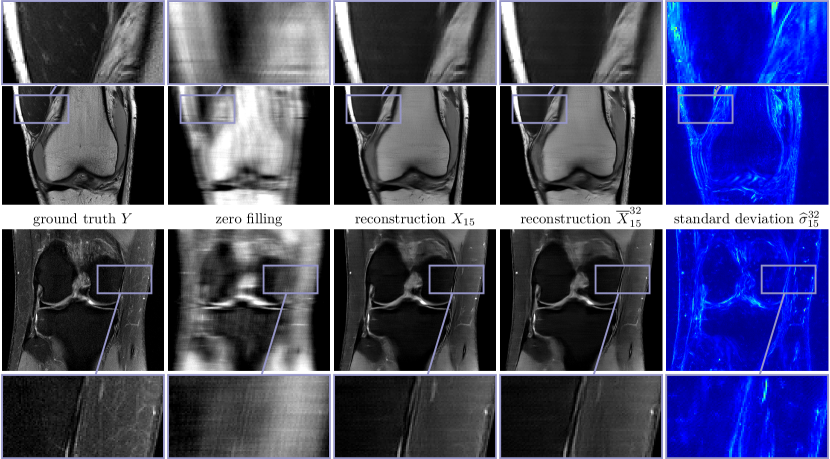

Figure 3 depicts two prototypic ground truth images of the PD data in the single (first row) and multi-coil (second row) case, the corresponding zero filling results, the deterministic X15subscript𝑋15X_{15} and the mean X¯1532superscriptsubscript¯𝑋1532\overline{X}_{15}^{32} with β=104𝛽superscript104\beta=10^{-4} for Q=1𝑄1Q=1 and β=7.5105𝛽7.5superscript105\beta=7.5\cdot 10^{-5} for Q=15𝑄15Q=15 (see (12)), and the standard deviation σ^1532superscriptsubscript^𝜎1532\widehat{\sigma}_{15}^{32} for an undersampling factor of R=4𝑅4R=4. The associated entropy levels are H¯(Σ)=11.90¯𝐻Σ11.90\overline{H}(\Sigma)=-11.90 and H¯(Σ)=13.68¯𝐻Σ13.68\overline{H}(\Sigma)=-13.68, respectively. In both the deterministic and the stochastic reconstructions even fine details and structures are clearly visible, and the noise level is substantially reduced compared to the ground truth, which can be seen in the zoom with magnification factor 333. Note that hardly any visual difference is observed in both reconstructions. Clearly, the quality in the single-coil case is inferior to the multi-coil case. Moreover, large values of the standard deviation are concentrated in regions with clearly pronounced texture patterns, which are caused by the lack of data in high-frequency k𝑘k-space regions. Thus, the standard deviation can be interpreted as a local measure for the epistemic uncertainty. Since the proximal operator is applied after the update of the regularizer, high values of the standard deviation can only be found in regions where data is unknown.

Figure 3: Single (first row) and multi-coil (second row) MRI reconstruction results for PD data and R=4𝑅4R=4. From left to right: ground truth images Y𝑌Y, zero filling, deterministic reconstructions X15subscript𝑋15X_{15}, stochastic reconstructions X¯1532superscriptsubscript¯𝑋1532\overline{X}_{15}^{32} and standard deviations σ^1532superscriptsubscript^𝜎1532\widehat{\sigma}_{15}^{32} (00 Refer to caption 0.020.020.02).